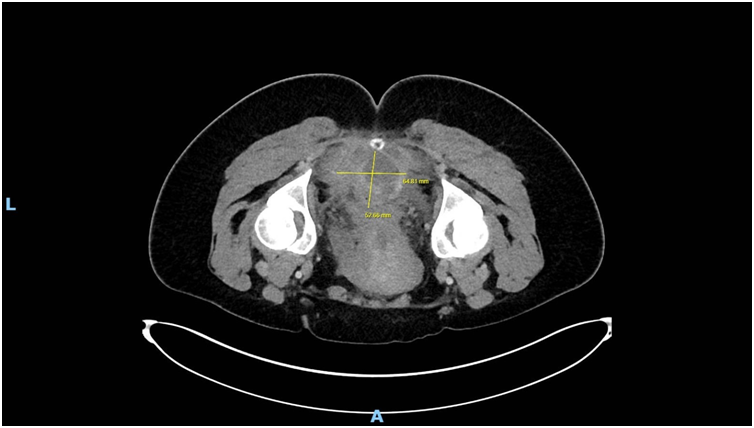

Imaging via MRI and CT demonstrated a complex, encapsulated lesion with peripheral enhancement and restricted diffusion. Multidisciplinary evaluation suggested a congenital epidermoid or duplication cyst. Given the absence of malignancy and surgical complexity, a conservative management strategy was adopted.

Figure 5: Figure 5 Duplication cyst axial 2020 plane post cystic aspiration

Figure 8: Figure 8 Duplication cyst 2020 axial plane